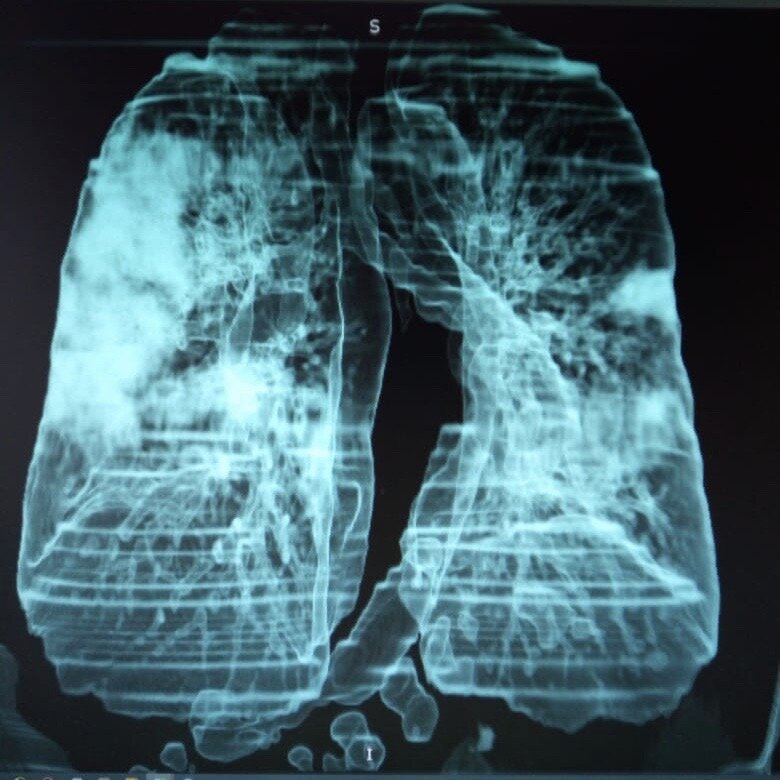

В большинстве случаев компьютерную томографию легких и бронхов проводят без использования контрастного вещества. В течение нескольких секунд сканирования томограф делает множество снимков грудной клетки с шагом, не превышающим 1 мм. Все сканы передаются на компьютер, который формирует из них трехмерное изображение исследуемого органа или участка тканей. Такая методика характеризуется достаточной информативностью и позволяет выявить практически все патологии на первых стадиях развития.

• 3D изображение тканей;

• максимальная информативность;

• возможность точного определения локации, размера и характера патологического очага;

• отсутствие слепых зон, позволяющее оценить состояние всех сегментов;

• возможность выявления новообразований на начальных этапах их развития с размером до 5 мм.